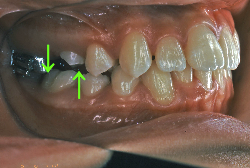

叢生(そうせい)

凸凹な歯並びのことを叢生といいます。矯正歯科に来院する患者様の主訴の中で、最も多いのが「配列の凸凹を真っ直ぐにしたい」というものです。歯の大きさと顎の大きさの調和がとれていないことが原因です。

凸凹を主体としたケースの場合、当院の平均治療期間は18ヶ月ですので、このケースは少し長めに経過しました。理由の一つは凸凹の程度がかなり重症だったと言うことですが、もう一つは、右下第2大臼歯が45度くらい前傾していたため、それを整直化させるために時間を要したと考えています。いずれにしても最終結果は大変よい状態と思います。

治療前は並びが乱れて見た目が悪いというのはもちろん問題ですが、歯科医学的に一番困るのは噛み合わせが悪いという点です。上下の犬歯(3番目の歯)は、上下的に離れた位置にあるため接触することができません。つまり歯としては存在していても、歯としては機能していないということです。